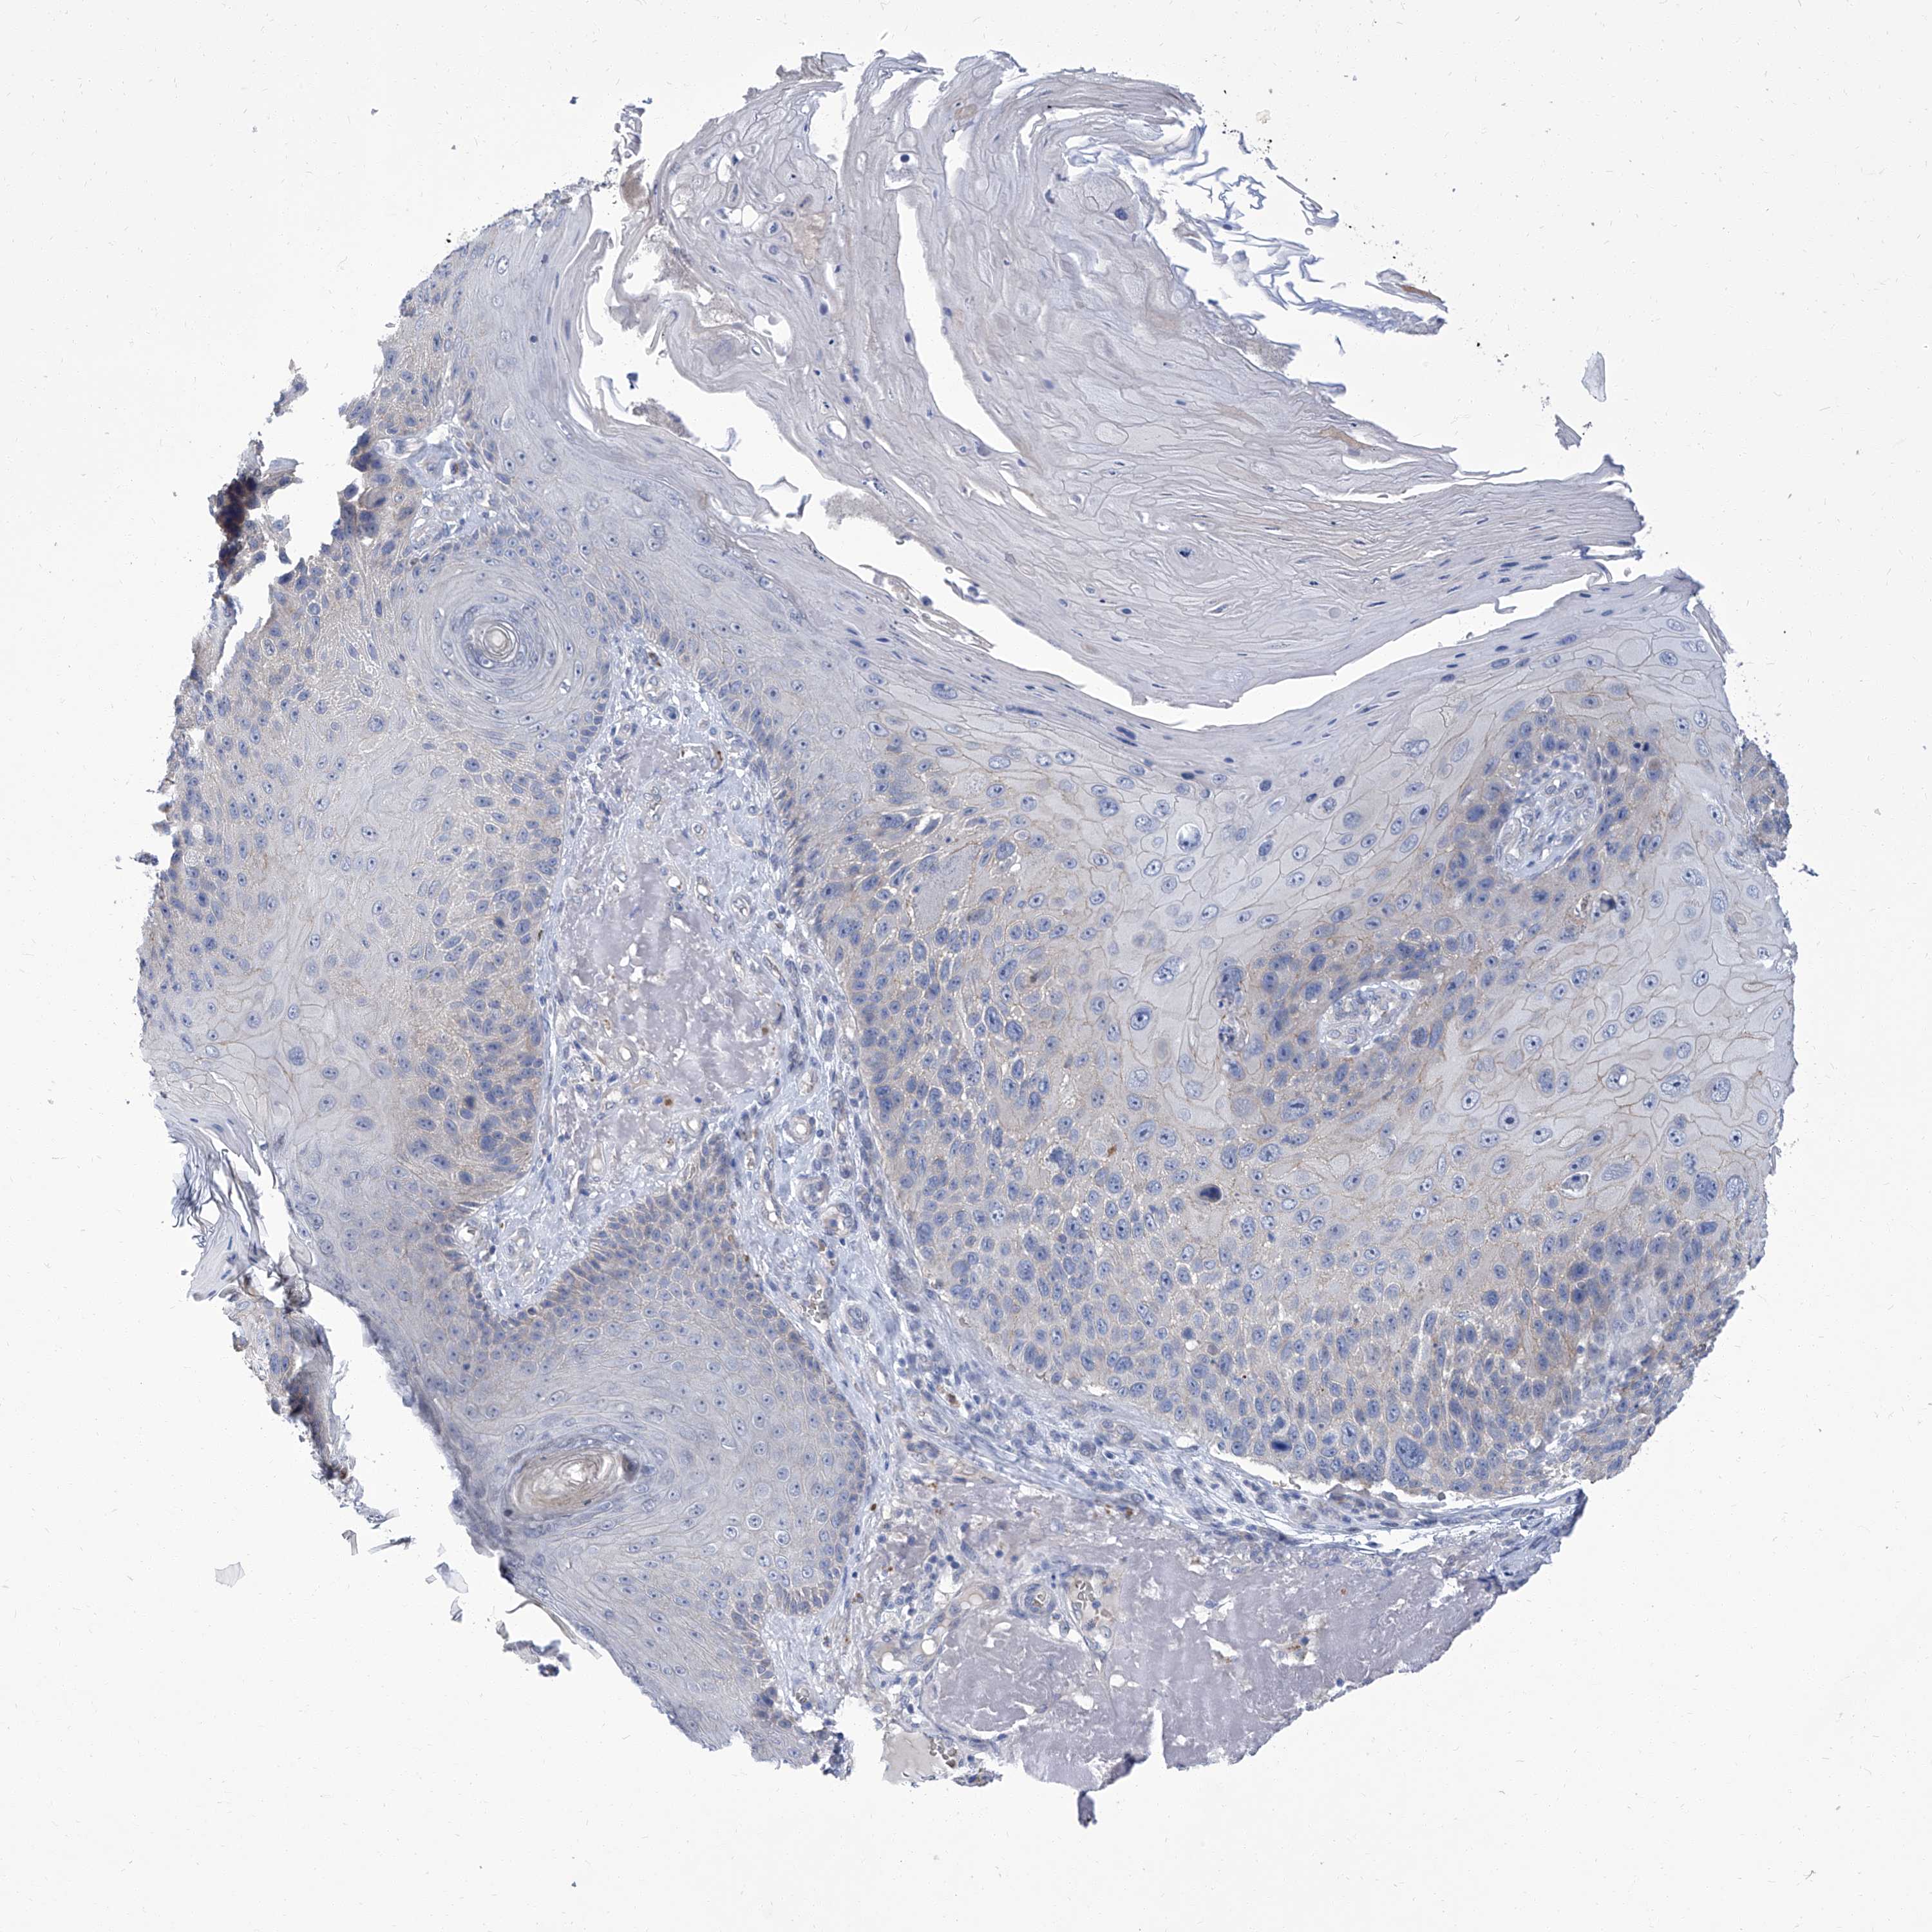

SKIN CANCER - Protein expressioni

A mouse-over function shows sample information and annotation data. Click on an image to view it in a full screen mode. Samples can be filtered based on level of antibody staining by selecting one or several of the following categories: high, medium, low and not detected. The assay and annotation is described here.

Each image is clickable and will lead to virtual microscopy that enables deeper exploration of all samples and also displays staining intensity scores, fraction scores and subcellular localization as well as patient and tissue information for each sample.

Antibody HPA030443

Staining

High

Medium

Low

Not detected

Intensity

Strong

Moderate

Weak

Negative

Quantity

>75%

75%-25%

<25%

None

Location

Nuclear

Cytoplasmic/membranous

Cytoplasmic/membranous,nuclear

Basal cell carcinoma